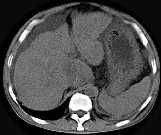

- 单项选择题男,44岁, 有乙肝病史,现腹胀, 右上腹痛,消化不良, 消瘦、乏力、贫血、黄疸,血清转氨酶升高, 清蛋白/球蛋白比值倒置。CT、MRI检查如下图,最准确的诊断是 ( )

A、肝硬化并腹水

B、肝硬化并腹水、再生结节

C、肝硬化腹水、肝癌

D、肝硬化并再生结节

E、肝硬化并腹水、脂肪肝